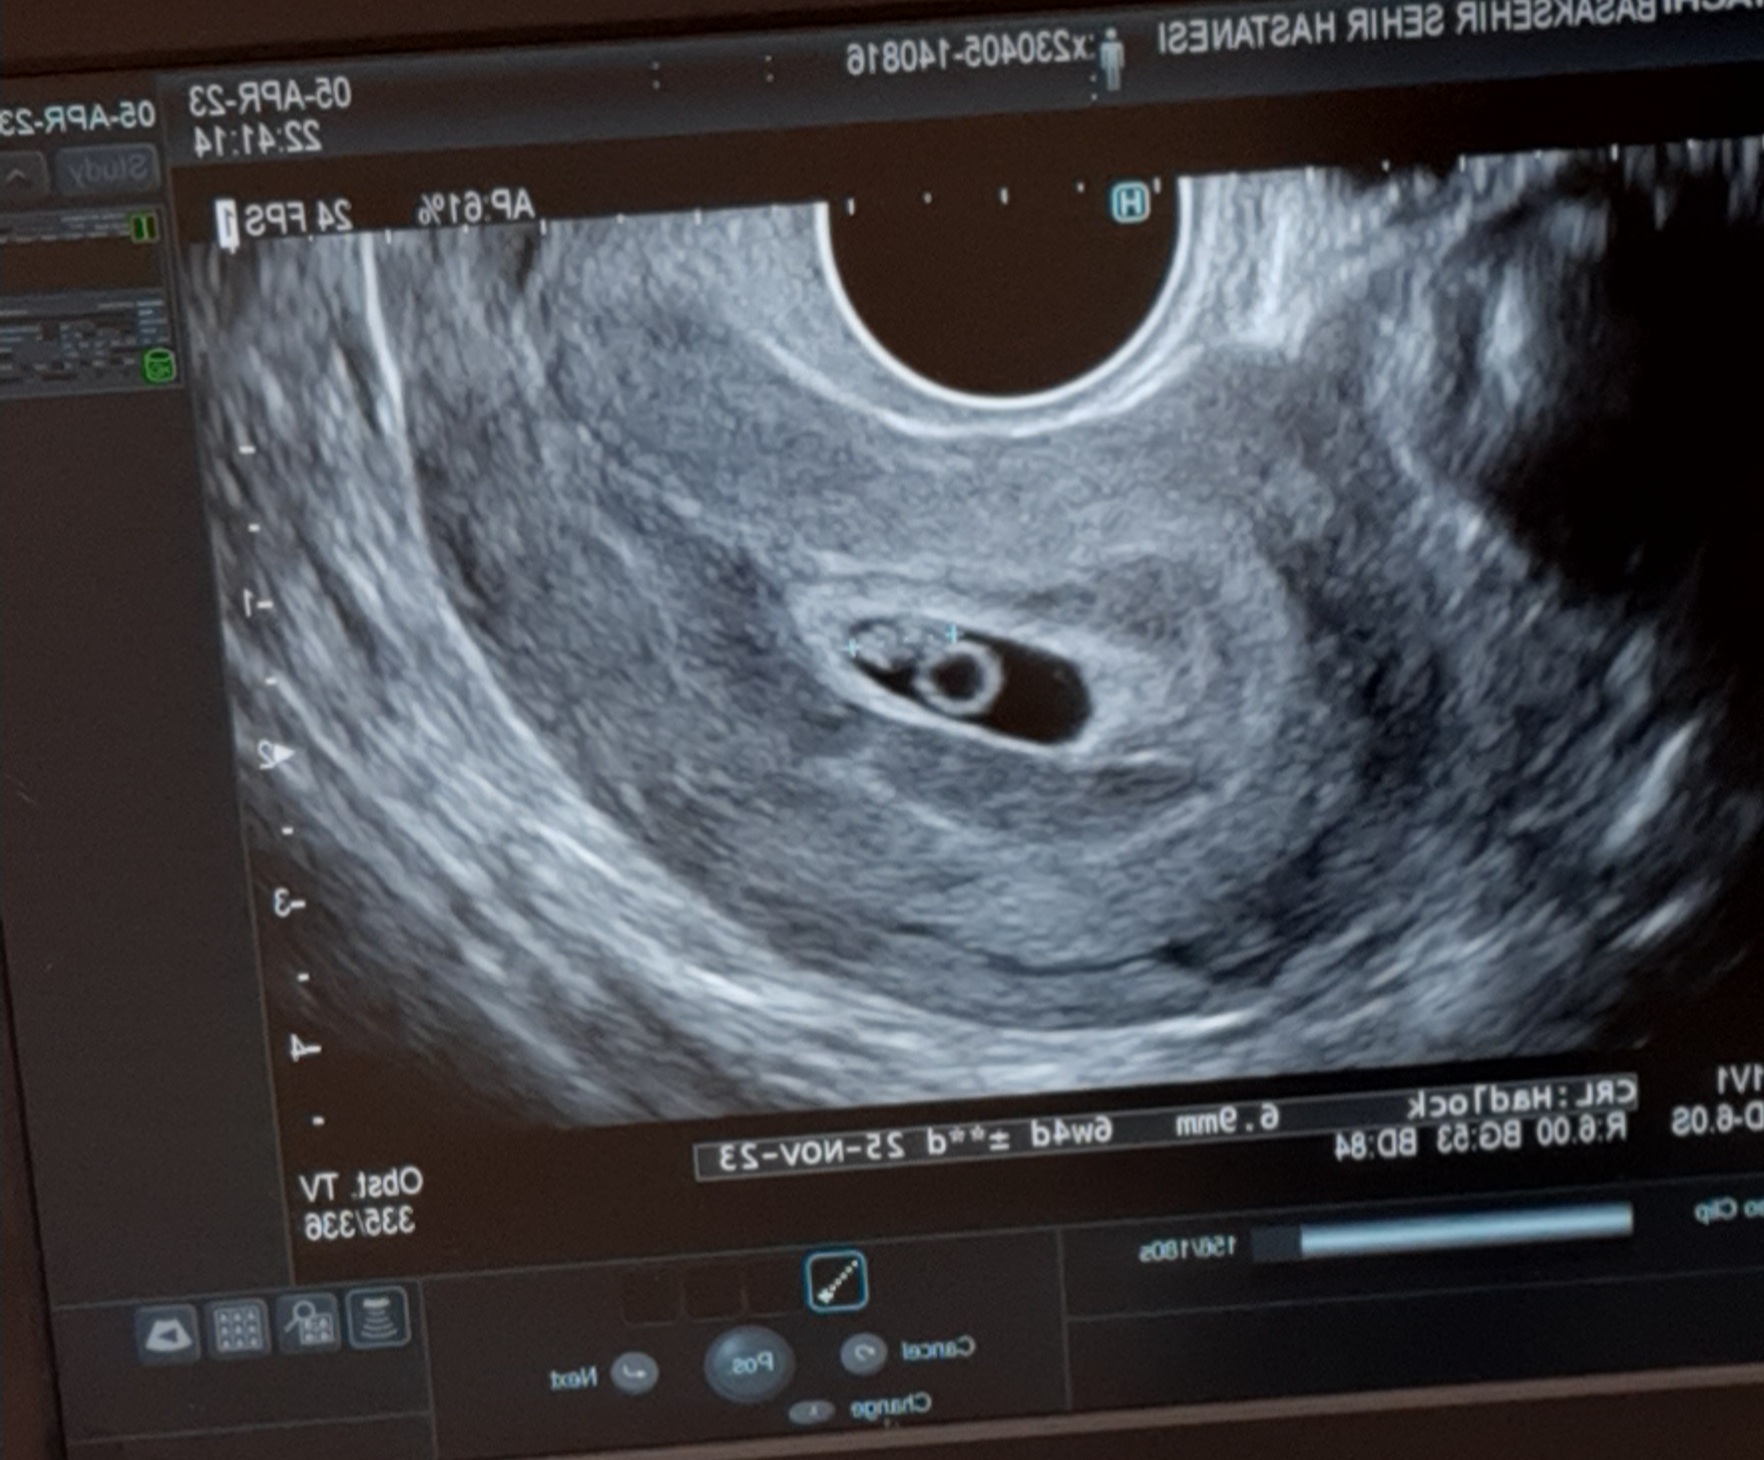

Kızlar gittim progestanı 2 katına çıkardılar kanama devam ederse hemen geri gel dedi doktor çok şükür bebeğim iyi ♥️ Bu da Minik Bebeğimin ilk resmi🥰Ekli dosyayı görüntüle 3795

6 hafta 4 gün sanırım